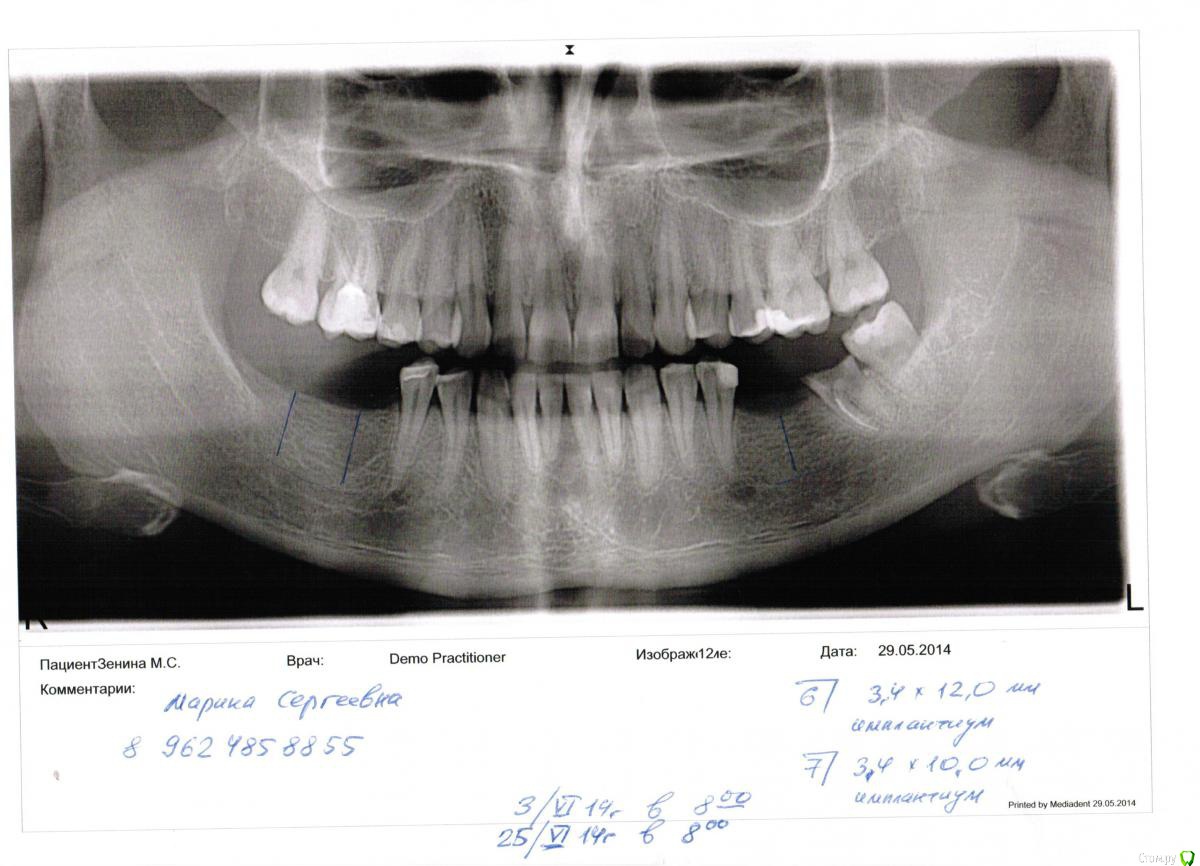

марин зенина Опубликовано 31 декабря, 2014 Автор Поделиться Опубликовано 31 декабря, 2014 (изменено) вот снимок. как то иголкой тыкали в десну еще и все. Изменено 31 декабря, 2014 пользователем марин зенина Ссылка на комментарий

марин зенина Опубликовано 31 декабря, 2014 Поделиться Опубликовано 31 декабря, 2014 Всем доброго времени суток! У меня вопрос к специалистам в области имплантации. Консультировалась в 5 клиниках и только в одной сказали, что нельзя такой узкий имплант ставить на жевательные зубы. Вобщем, ситуация такая. У меня нет 6.7.8 на нижней челюсти с одной стороны и с другой стороны нет 6. на одной стороне сказали, что точно наращивание кости, а с другой сказали можно на 6 - 3.4*12мм и на 7 - 3.4*10мм. 4 имплантолога готовы были поставить мне эти импланты и лишь одна сказала, что такие узкие нельзя ставить, т.к. они года через 2-3 начнут шататься. Скажите, пжста, это реально так? Ссылка на комментарий

SDC Опубликовано 31 декабря, 2014 Поделиться Опубликовано 31 декабря, 2014 у меня есть только панорамный, кт делать не говорилиА как были определены размеры кости? По ортопантомограмме? ОПТГ имеет искажения до 20% и нет возможности определить ширину кости 1 Ссылка на комментарий